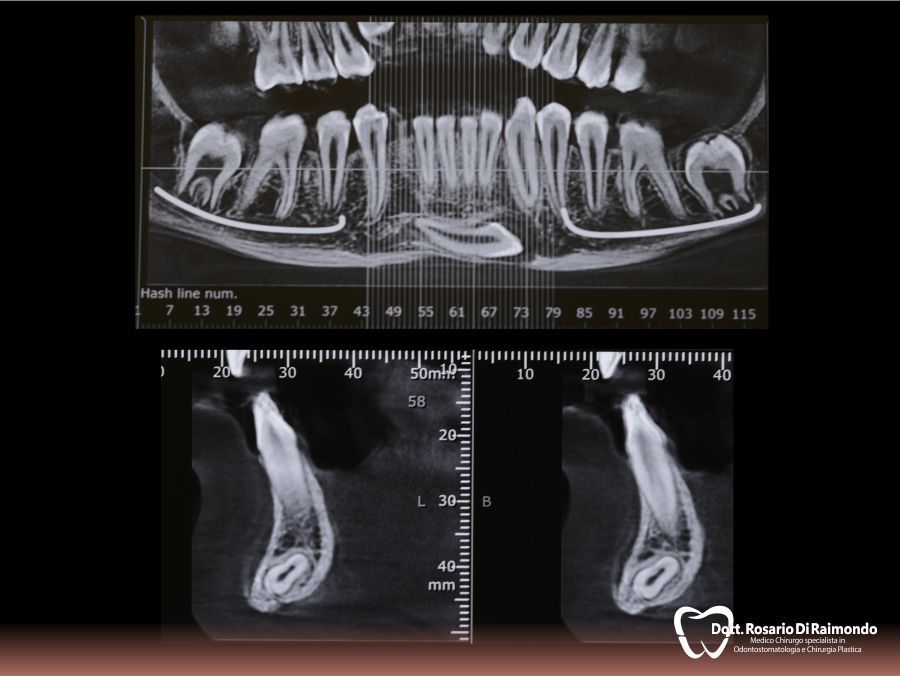

Casi Trattati

Di seguito riportiamo alcune fotografie di casi esplicativi di Chirurgia Orale.